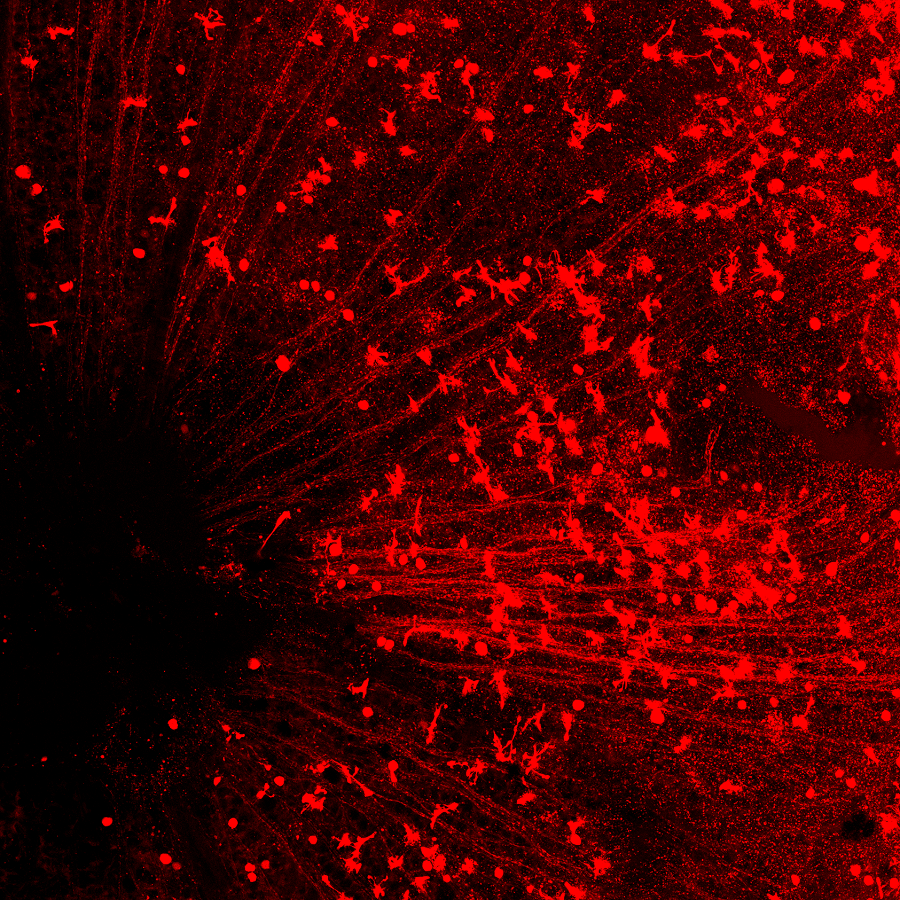

图注:(上)CasRx通过靶向的降解Ptbp1 mRNA从而实现Ptbp1基因表达的下调。(中)视网膜下注射AAV-GFAP-CasRx-Ptbp1可以特异性的将视网膜穆勒胶质细胞转分化为视神经节细胞,转分化而来视神经节细胞可以和正确的脑区建立功能性的联系,并且提高永久性视力损伤模型小鼠的视力。(下)在纹状体中注射AAV-GFAP-CasRx-Ptbp1可以特异性的将星形胶质细胞转分化为多巴胺神经元,从而基本消除了帕金森疾病模型小鼠的运动症状。

在小鼠的视网膜上,红色圆形的细胞是再生出的视神经节细胞,可以看到一条一条的红线汇集到眼睛中间的视盘(左下黑洞区域),这是再生出的视神经节细胞发出的轴突,它们将通过视盘传到视神经,然后再到大脑。